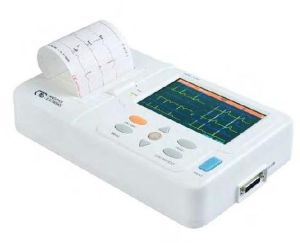

RS Enterprises is one of the noteworthy suppliers of a wide array of highly operational machines. We deal in EMG machine, ECG machine, Neuro Modulation Machine, Digital Biofeedback Machine, Therapy ECT Machine, Transcranial Magnetic Stimulation Machine, Sleep Study Machine, Pulmonary Function Test Machine, Digital Polygraph Machine, Digital Physiograph Machine, Digital Plethysmometer Machine, AD629 Diagnostic Audiometer, AD226 Diagnostic Audiometer, Channel ECG Machine, Electric OT Table and many more. As a respected name in the industry, we procure the entire range of products only from the reliable manufacturers or vendors after checking against numerous quality parameters such as functionality, maintenance, manufacturing defect, etc. We are capable of undertaking bulk as well as urgent orders as we maintain a streamlined inventory management system.